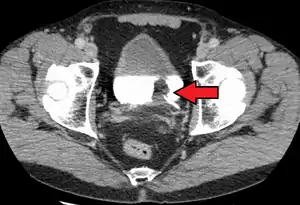

The most common sites for bladder cancer metastases are the lymph nodes, bones, lung, liver, and peritoneum.[78] The most common sentinel lymph nodes draining bladder cancer are obturator and internal iliac lymph nodes. The location of lymphatic spread depends on the location of the tumors. Tumors on the superolateral bladder wall spread to external iliac lymph nodes. Tumors on the neck, anterior wall and fundus spread commonly to the internal iliac lymph nodes.[79] From the regional lymph nodes (i.e. obturator, internal and external lymph nodes) the cancer spreads to distant sites like the common iliac lymph nodes and paraaortic lymph nodes.[80] Skipped lymph node lesions are not seen in bladder cancer.[79]

- N1 Metastasis in a single lymph node in true pelvis (hypogastric, obturator, external iliac, or presacral nodes)

- N2 Metastasis in multiple lymph nodes in true pelvis (hypogastric, obturator, external iliac, or presacral nodes)

- N3 Metastasis in common iliac lymph nodes